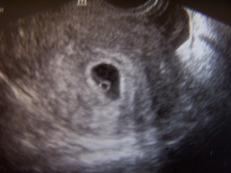

Jaj, képzeljétek hogy jártam kint! Két nacit vittem magammal, egy régi vékonyat, és az egyik kismama farmernacit. Na, a régi gatyómat 1x vettem fel, de olyan kényelmetlen volt, hogy egész nap kigombolva, és félig lehúzott cipzárral mászkáltam, még jó, hogy hosszabb polót vettem fel. A farmer meg sajna még nagy, ezért csak egy övvel tudtam hordani, ami meg nyomta a pocakomat, de megígérte a férjem, hogy megcsinálja nekem. Szóval, nőtt az pocakom! Bár, a drága anyukám tegnap közölte velem, hogy nem is nagyon látszik még a hasam...

Szerintetek?

15+1